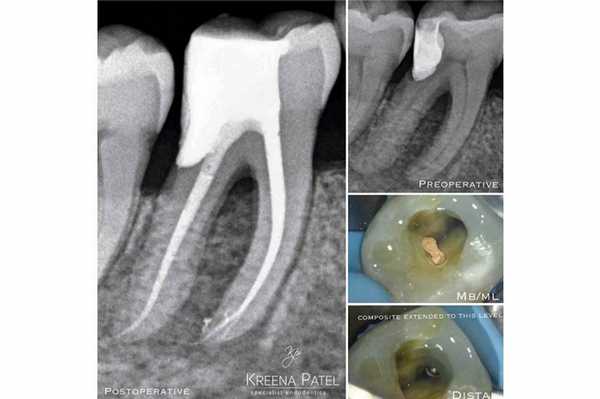

Когда следует проводить DME для зубов, требующих эндодонтического лечения?

Перед проведением эндодонтического лечения важно оценить, можно ли вообще восстановить зуб. Для этого первоначально нужно удалить весь кариес и прежние реставрации, а также установить, можно ли обеспечить выполнение новых герметичных реставраций. В процессе врач может провести DME и выполнить преэндодонтическую подготовку зуба. После лечения корневых каналов на край композитной пломбы может быть установлена непрямая реставрация. При выполнении преэндодонтического восстановления не всегда можно сформировать адекватный контакт (фото 4). Но на данном этапе это не так и важно, поскольку контактный пункт может быть восстановлен за счет окончательной реставрации. Куда более важно - удалить все нависающие края материала, поскольку они в последствии могут вызвать развитие пародонтальных проблем. Процедуру удаления излишков можно провести или скальпелем, или очень тонким бором. Если же зуб планируется восстановить лишь за счет композитной реставрации, то контактный пункт можно сформировать в конце, просто заново восстановив стенку, но уже с уровня, сформированного в ходе DME.

Фото 4. Лечение корневого канала, установка стекловолоконного штифта и восстановление культи зуба LL5. Глубокий край дефекта был восстановлен посредством DME. Контактный пункт будет откорректирован на финишном этапе реставрации.

Какие материала использовать для прямой реставрации?

Техника DMЕ изначально была разработана для восстановления глубокого края дефекта зуба посредством композитного материала. Ведь при фиксации непрямой окончательной реставрации за счет адгезивной связи таковая может «приклеится» непосредственно к поднятому из глубины композитному краю. Концепция DME также может быть реализована и за счет амальгамы или стеклоиономерного цемента. Для оценки адаптации реставраций необходимо использовать рентгенографию «в прикус» (bite-wing): это позволяет идентифицировать нависающие края или «недолеты» композитного восстановления.

Почему DME важно для эндодонтии?

В эндодонтии врачи часто встречаются с зубами, один из краев дефекта которых находиться глубоко под деснами. По сути, DME дает шанс зубу «выжить», ведь без подобного подхода такой зуб можно категоризировать как такой, что не подлежит восстановлению (фото 7). Эффективное восстановление глубокого края дефекта часто является наиболее сложной частью лечения и занимает больше всего клинического времени.

Фото 7. Пациент обратился за стоматологической помощь по поводу кариеса корня и возможности восстановления зуба LR6. В ходе первого визита был очищен весь кариес и удалена старая пломба, после чего приступили к DME. Эндодонтическое лечение проводили в ходе второго визита. В дистальный канал установили стекловолоконный штифт, а всю дистальную поверхность восстанавливали посредством композита. Пациент был направлен к лечащему врачу для изготовления непрямой реставрации.